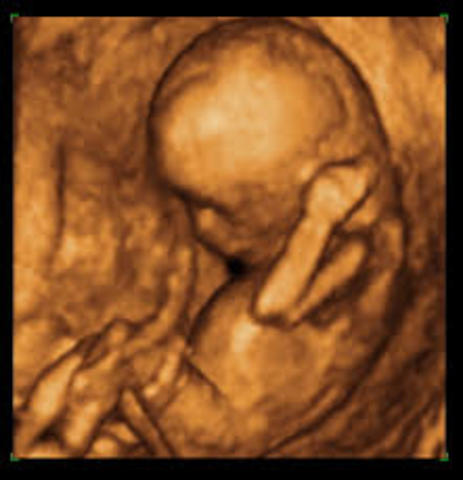

• semana 8 y 9 de embarazo

semana 8 y 9 de embarazo

Hacia el final de la semana 8 el cuerpo estará formado, así como tosoa sus órganos y terminará el periodo embrionario. Dejará de ser un embrión para convertirse en feto en la semana 9 crecen los dedos de las manos y de los pies. La cabeza es desproporcionalmente grande y construye la mitad del embrión. La región del cuerpo se ha formado. T5iene un cuerpo muy flexible ya no tiene huesos.